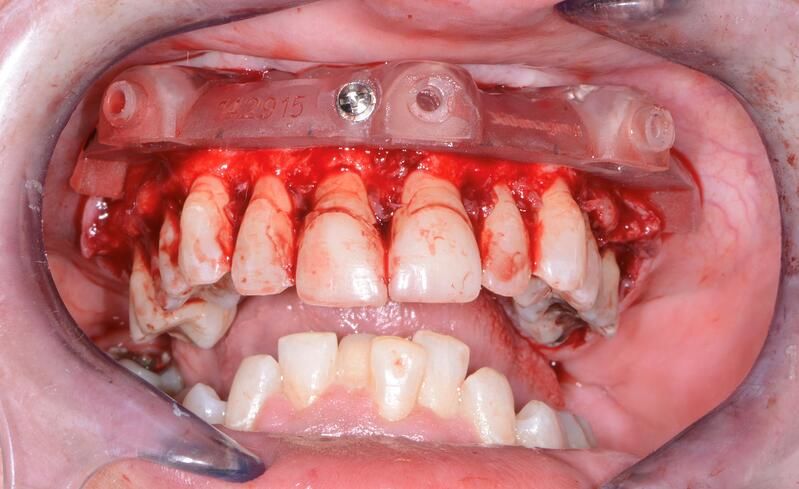

全口組合式導(dǎo)板病例

術(shù)中過(guò)程